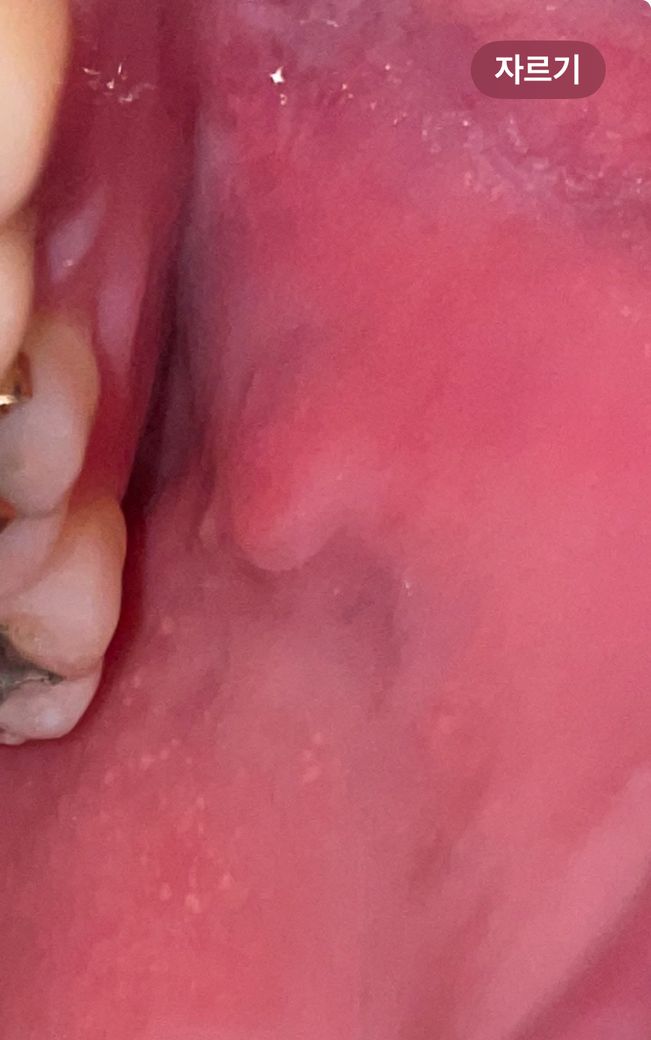

구강 볼 안쪽 점막에 하얀 돌기들과 통증은 어떤 질병인가요?

따끔 거리고 화끈거리는 통증이 있는데 이게 편평태선이라는 질병인지 홍반증인지 궁금합니다 없어지지 않고 있는데 냅둬도 되는 건가요 구강암으호 변하는 질병은 아니겠죠? 왼쪽 볼에만 있습니다 혹시나 잘때 이갈이 장치를 착용하는디 그거때문에 생긴 건가요?

하얀 돌기와 통증이 있는 증상은 여러 가지 원인에 의해 발생할 수 있습니다만, 장치를 새로 착용하게 된 경우, 구강 점막에 자극이 가해져 증상이 발생했을 가능성이 있습니다.

구강암은 일반적으로 증상이 호전 없이 지속되는 양상을 보이기 때문에, 증상이 2주 이상 지속된다면 구강내과 진료를 제공하는 치과에서 진료를 받아보시는 것이 좋겠습니다.